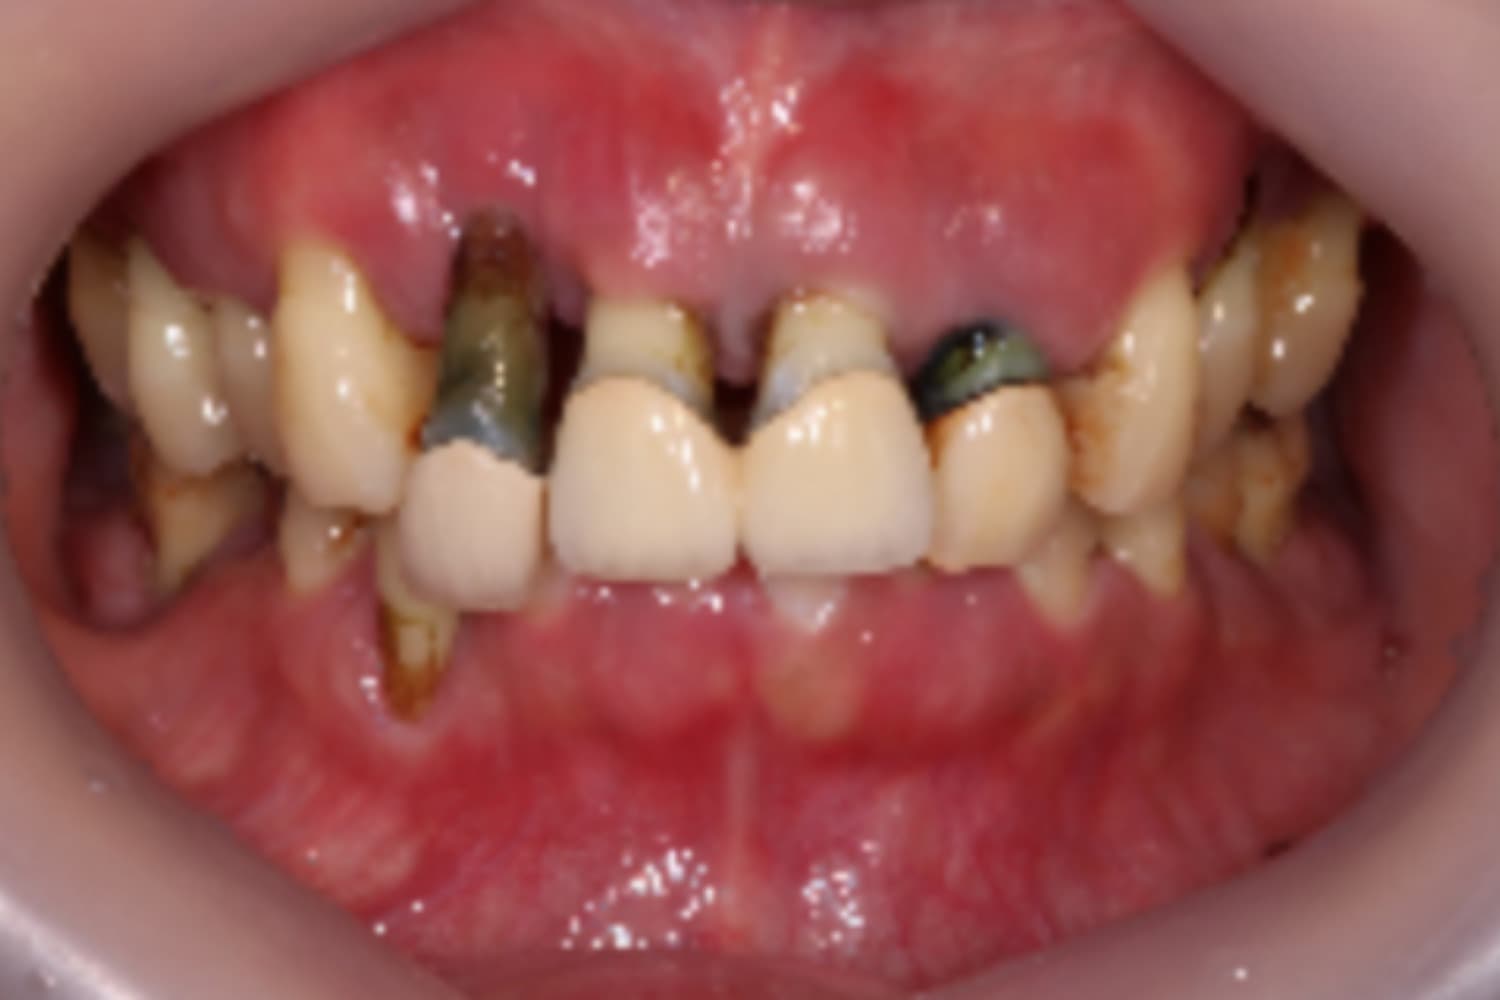

前歯のインプラント治療

Before

After

前歯4本を抜歯し、その後2本のインプラントと骨造成を行いました。上部構造は4本分です。

主訴

前歯が気になる

治療期間

12カ月

治療回数

12回

費用

1,276,000円

副作用・リスク

・重度歯周病により、感染リスクが高い ・インプラントとの結合不良が起きる可能性がある ・手術前に歯周病の十分なコントロールが必要 ・治療後も1〜2カ月ごとの定期メインテナンスが必須